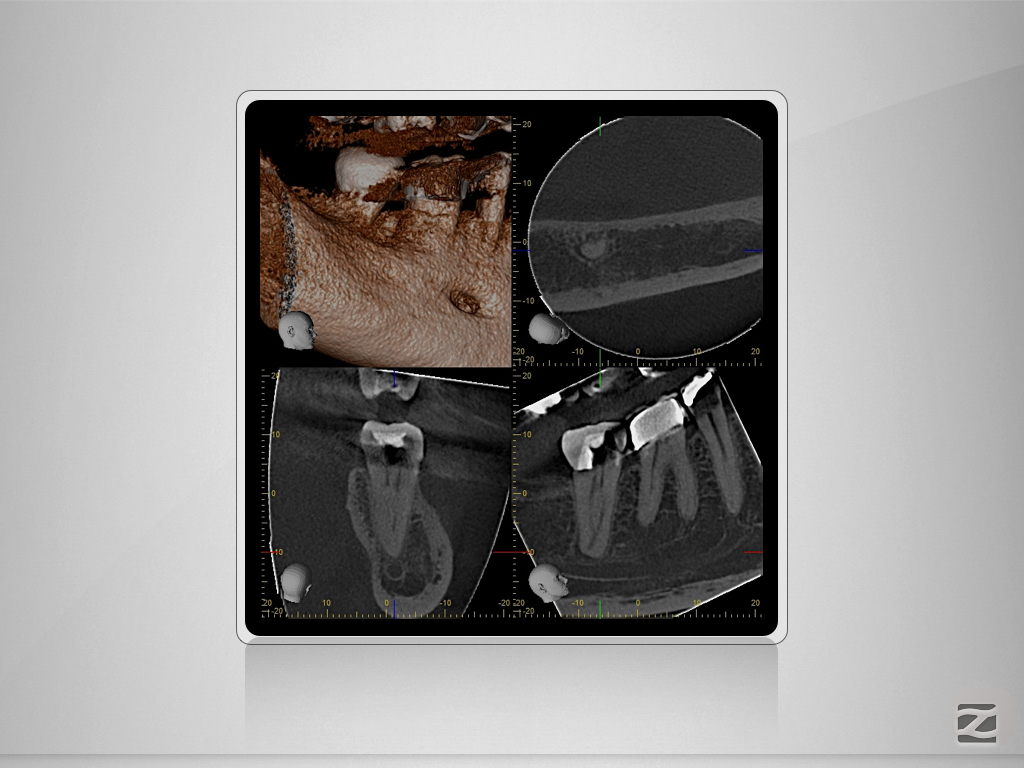

47d-008

„C“ ja – „C“ nein